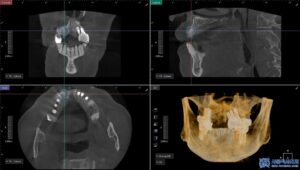

다만, 환자분의 경우

치조골이 많이 부족한 상태여서

임플란트 식립과 동시에 뼈 이식도

함께 진행하기로 했습니다.

이 과정에서 환자분께

가장 적합한 방법인

무절개 임플란트로

치료를 진행하였습니다.

태평동치과 서울박사는 기본적으로

무절개 방식으로 임플란트를 진행하고 있으며,

이는 특히 당뇨가 있으시거나 고령으로 인해

상처 치유가 느린 분들께

권장되는 치료 방법입니다.